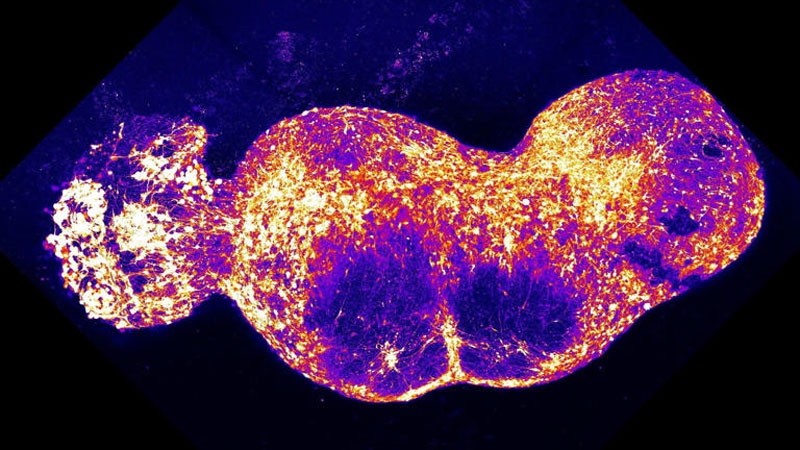

Все четыре органоида были помещены в чашку для культивирования, где срослись, образовав непрерывный контур передачи нервного импульса от начала до конца. На это ушло около 100 дней, в результате чего был сформирован ассемблоид длиной почти 1 см, содержащий около 4 млн клеток. Нейронные связи объединили составные органоиды, и в системе возникли паттерны синхронной передачи сигналов.